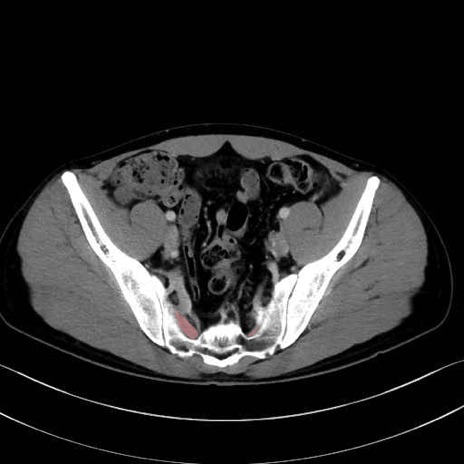

外閉鎖筋 (Obturator externus)